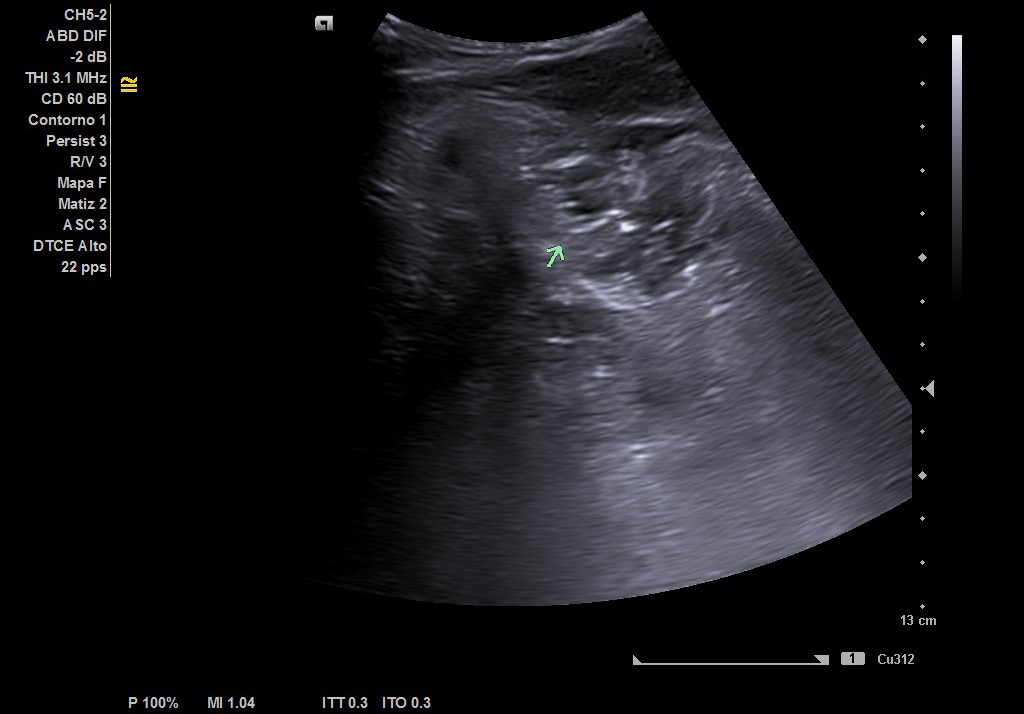

Hallazgos ecográficos

Hígado de tamaño, forma y ecoestructura conservadas, con parénquima homogéneo. Vena porta de calibre conservado.  Ausencia de signos de dilatación de la vía intra o extrahepática. Vesícula biliar de paredes finas, sin contenido ecogénico en su interior. Páncreas de características normales. Riñones de tamaño y localización conservada, sin hidronefrosis. En FID imagen heterogénea delimitada, de 50x30 mm, con posible edema de pared y focos ecogénicos en su interior.

Complicaciones post-quirúrgicas (Plastrón inflamatorio vs absceso). Diagnóstico diferencial: Diverticulitis colon derecho. Tras ecografía realizada por Radiología en el servicio de Urgencias y valoración por Cirugía General se llegó al diagnóstico de plastrón inflamatorio y colección postapendicectomía.